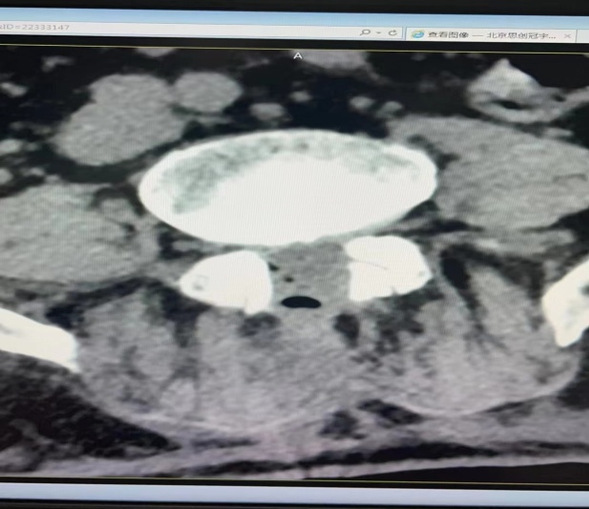

术后CT片子

术后24小时,李先生就可以下床活动了,并且之前的症状全都消失了。现在李先生已经回归正常生活,每天脸上都洋溢着灿烂的笑容。